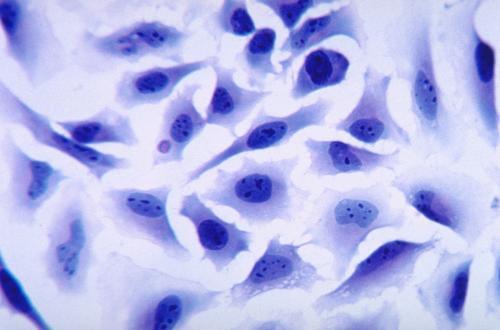

腫瘤免疫中的免疫抑制性細胞因子

關注小藥說藥,一起成長!前言癌細胞表觀遺傳學和生長動力學的改變導致細胞外分泌多種細胞因子,這些細胞因子控制免疫細胞的活性,使其有利于腫瘤生長。其中,免疫調節細胞因子的分泌是招募免疫抑制細胞的主要因素。腫瘤微環境中的免疫調節細胞因子招募其他免疫抑制細胞,并負責效應免疫細胞的表型和功能轉換,使其支持腫瘤的發展。表型轉換的免疫細胞進一步提高免疫抑制細胞因子的水平,并使腫瘤環境抵抗抗腫瘤免疫細胞的活性。其